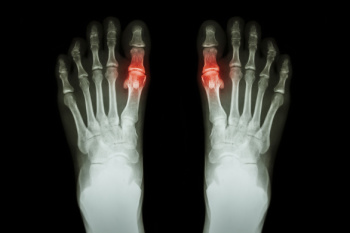

Gout is a common and acute form of inflammatory arthritis that often shows up first in the foot, especially the big toe. The toe may look red and shiny, and feel warm, sometimes with tight skin that appears stretched. It often feels like sudden burning pain, throbbing, and extreme tenderness, even to light touch or sheets. Symptoms can arrive quickly and flare at night. Causes include high uric acid levels, kidney issues, and diets high in purines, such as red meat, shellfish, and alcohol. A podiatrist can help from the start by confirming the diagnosis through history, imaging, and laboratory testing when needed. Treatment may begin with pain relief, anti-inflammatory care and footwear advice. It may then move into long-term management, lifestyle education, and coordination with medical providers. Early care can reduce damage and recurrence. If you are dealing with painful gout, it is suggested that you make an appointment with a podiatrist.

Gout is a type of arthritis caused by a buildup of uric acid in the bloodstream. It often develops in the foot, especially the big toe area, although it can manifest in other parts of the body as well. Gout can make walking and standing very painful and is especially common in diabetics and the obese.

Gout can easily be identified by redness and inflammation of the big toe and the surrounding areas of the foot. Other symptoms include extreme fatigue, joint pain, and running high fevers. Sometimes corticosteroid drugs can be prescribed to treat gout, but the best way to combat this disease is to get more exercise and eat a better diet.